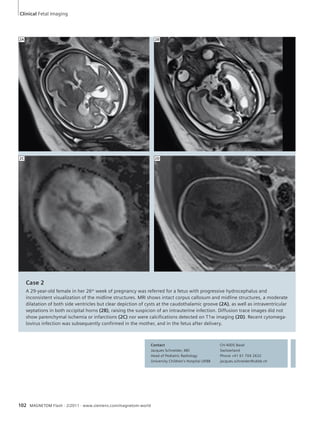

Fetal Imaging

100 Case Series: Fetal MR Imaging

Jacques F. Schneider